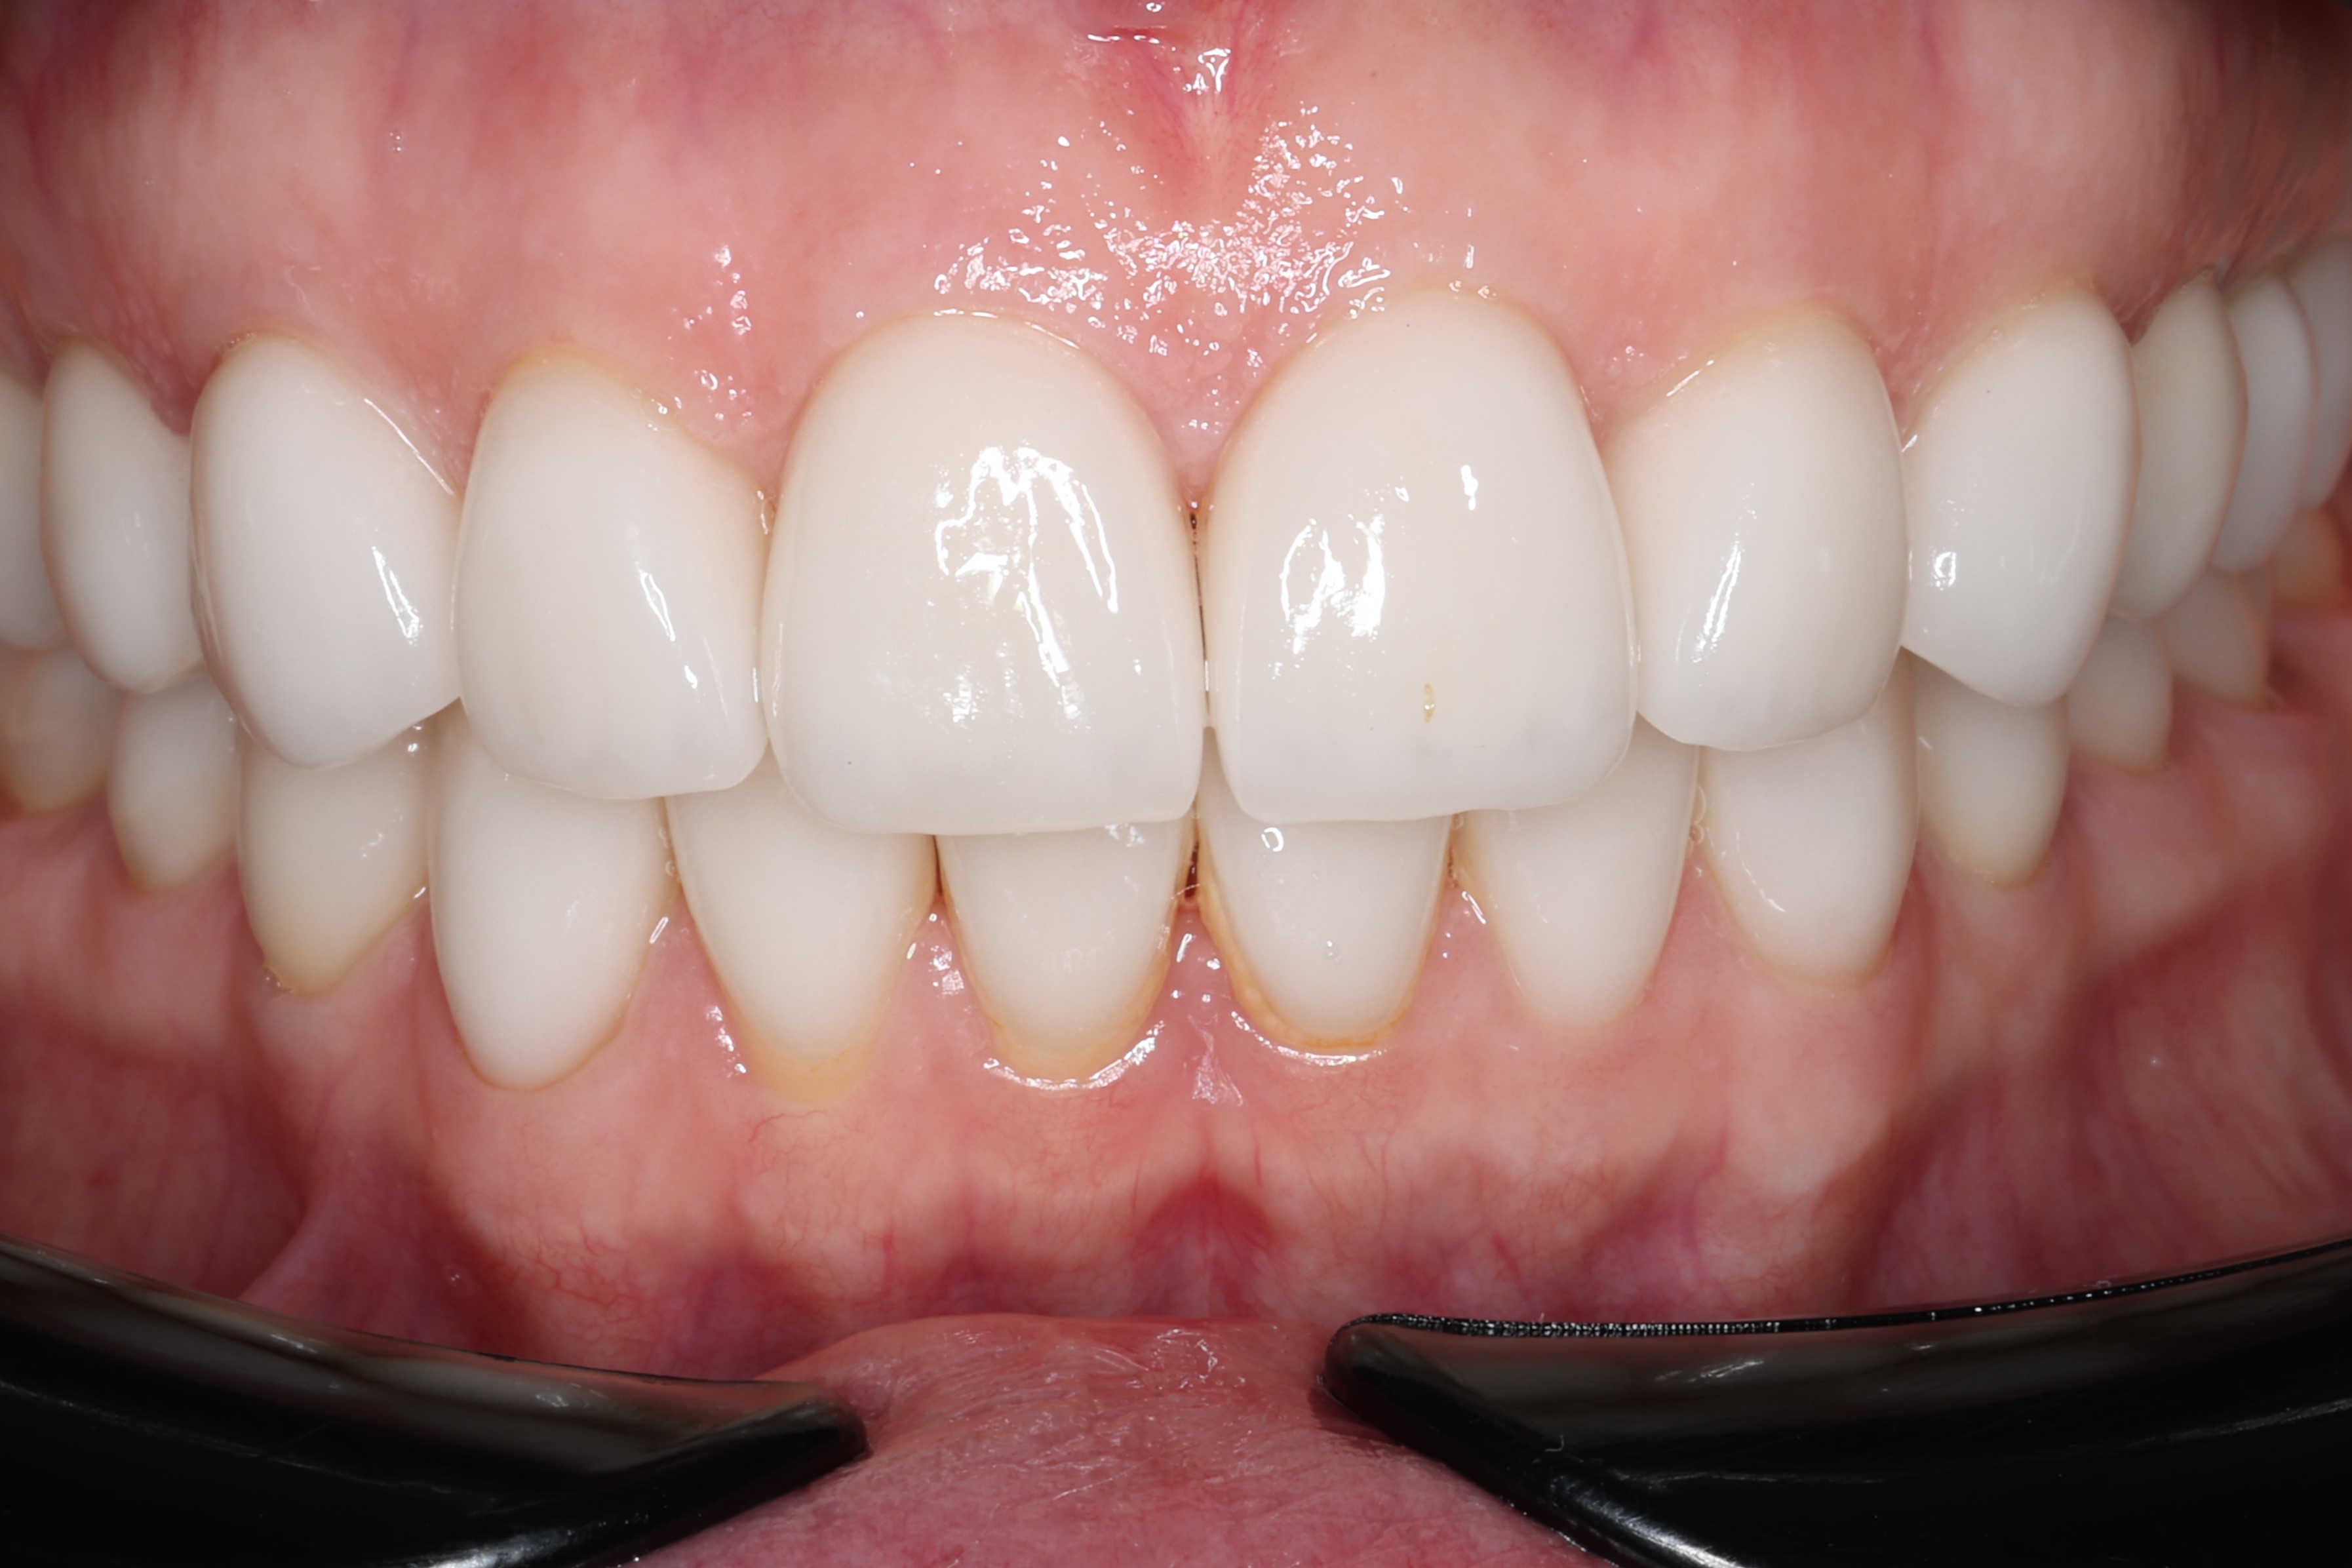

Спустя шесть  месяцев после закрытия рецессий десны.

На этом пациента можно считать реабилитированным. В дальнейшем осмотры проводятся разв год.